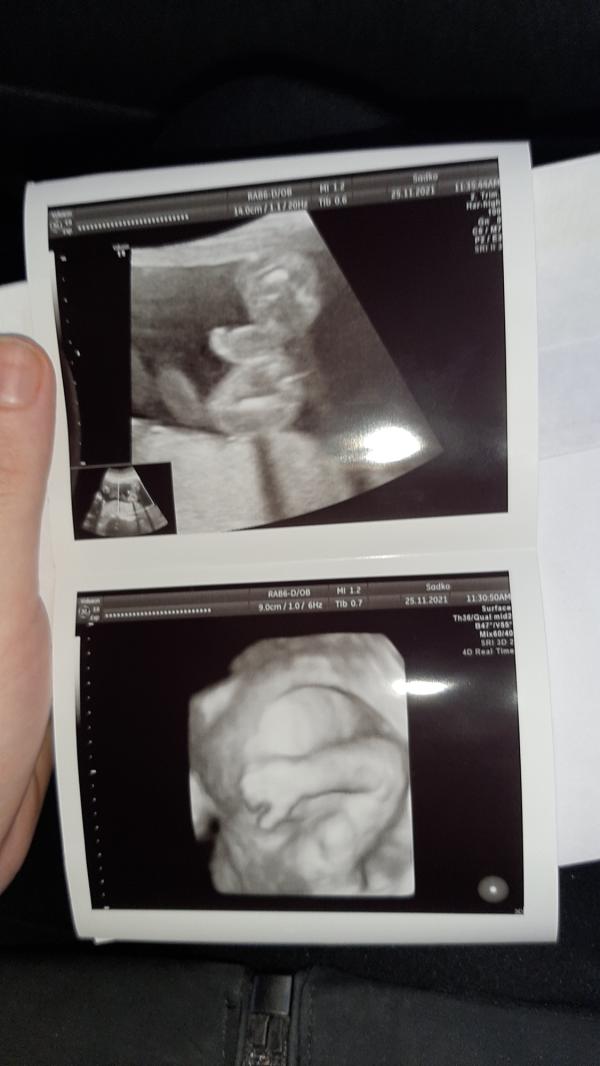

Сегодня был второй скрининг.

20 недель и 3 дня

Сказали 100% мальчик, как и хотели с папой😍

Ждем наше маленькое ЧУДО!🥰